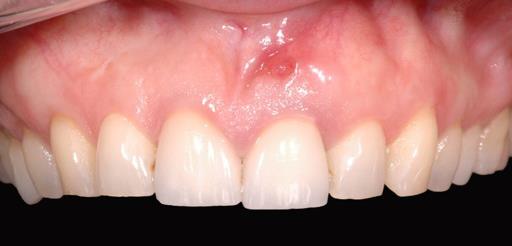

16/18 - Final restoration 15 months after implantation and stability of root coverage in regio 23GBR together with soft tissue augmentation with mucoderm® and maxresorb® - Dr. S. Scherg